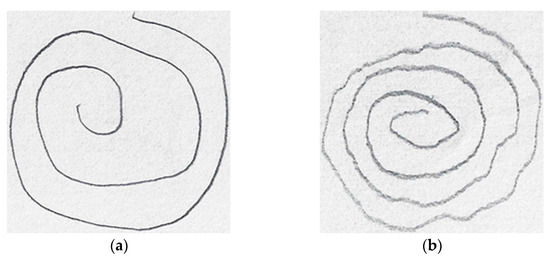

In [54], Shaban investigated the use of a fine-tuned pre-trained VGG-19 to distinguish between PD and controls based on wave and spiral handwriting datasets. The proposed model achieved an elevated accuracy and sensitivity of over 88% and 86%, respectively. Figure 8 shows the spiral drawing created by a healthy control and a PD subject.

Figure 8.

Spiral drawings from (a) a healthy control (b) a PD subject.

It is clear from Figure 8 that the spiral drawing made by a PD subject shows the motor symptom manifestation of the disease (i.e., tremor, muscle stiffness, and slowness of movement).